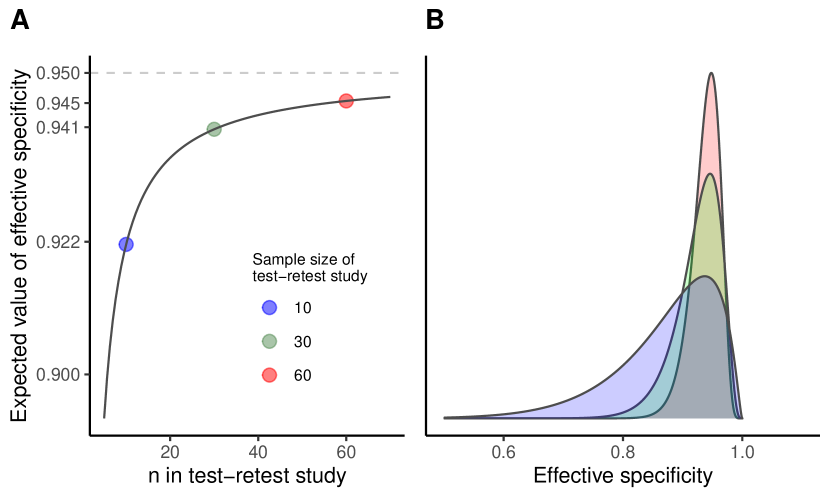

We need to be aware that even if is close to , i.e. the bias is low, the probability for a substantial deviation of the actually realized specificity from the targeted specificity might be large (Figure 1).

This can also be concluded from Figure 4 A. Numerical solution of the exact formula (16) yields a sample size of 54. Resulting sample sizes for other values of can be taken from Figure 4 B. The resulting scenario in terms of the distribution of the relative error in the estimation of and its effect on is displayed in Figure 5 A.

B) Sample size resulting from (16) for different values of the desired lower bound that shall be exceeded with a fixed confidence of 95%.

Common sample sizes in test-retest studies are around 10 and 20 [3, 12, 22, 15, 4, 21]. If the point estimator of resulting from a test-retest study with a sample size of 10 and two repeated measurements is used, the distribution of the effective specificity will have prominent tails as illustrated in Figure 1. According to (17), the lower bound of the effective specificity obtained with 95% confidence is 0.7814 and 0.8512 for a sample size of 10 and 20, respectively, which might be insufficient (Figure 4). Note that for the recommendation by Obuchowski and Bullen[24] of a sample size of 35 for test-retest studies with the probability of achieving an effective specificity below 94% is 39.74%.

However, using the mean effective specificity as sole quality criterion has limitations, since the whole distribution of the effective specificity is not properly taken into account. As illustrated in Figure 1, there is a high probability that the actually achieved effective specificity deviates strongly from its target even if the mean effective specificity may be close to the targeted specificity. Therefore, we propose a quality criterion for sample size calculations based on the probability that the effective specificity exceeds a chosen lower bound, taking into account the tails of the distribution of .